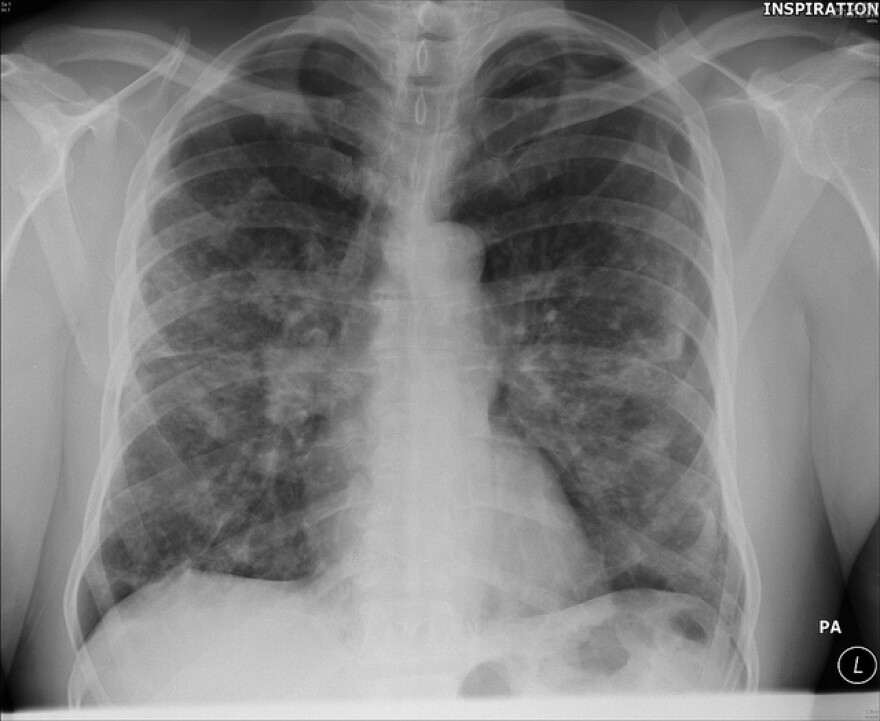

What You Should Know About Sarcoidosis | KERA News

Source: keranews.org

sarcoidosis lung pulmonary pathology should lesions nodular rosen yale.